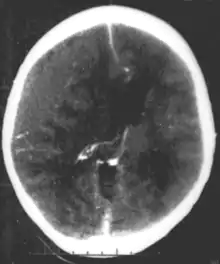

CT scan showing epidural hematoma, a type of traumatic brain injury (upper left)

Brain trauma in the developing human is a common cause (over 400,000 injuries per year in the US alone, without clear information as to how many produce developmental sequellae)[36] of neurodevelopmental syndromes. It may be subdivided into two major categories, congenital injury (including injury resulting from otherwise uncomplicated premature birth)[37] and injury occurring in infancy or childhood. Common causes of congenital injury are asphyxia (obstruction of the trachea), hypoxia (lack of oxygen to the brain), and the mechanical trauma of the birth process itself.[38]